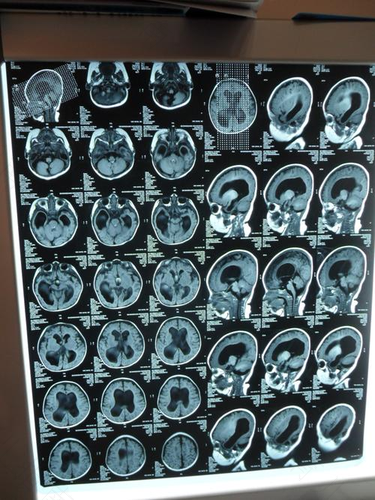

脑脊液产生过多或者是脑脊液吸收障碍都会导致中枢神经的感染,出现蛛网膜下黏连等一系列的问题,这些问题都会导致孩子脑积水的情况。一般这些通过检查都会发现,所以女性朋友不必对此过度担心,产生恐惧心理。